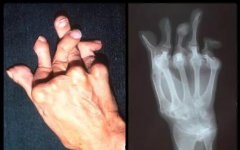

据国家卫健委统计,目前我国风湿骨病患者数量约为2.5亿人,重症患者有8000万人,其中约有53%的痛风、类风湿患者因疾病导致肢体残疾,肢体残疾了就意味着丧失了劳动能力,丧失劳动力的同时也就没有了经济来源。因此,因病致残、因残致贫的恶性循环是大多数风...[详细] 2021-07-09

风湿病发病率高、致残率高,被称为世界头号致残性疾病。最主要的原因之一就是由于多样复杂的发病因素和受治疗技术、治疗条件的限制,大多数患者因为没有条件接受系统、规范的治疗,病情得不到有效控制而最终导致身体残疾。据国家卫健委统计,目前我国风湿病...[详细] 2021-07-07